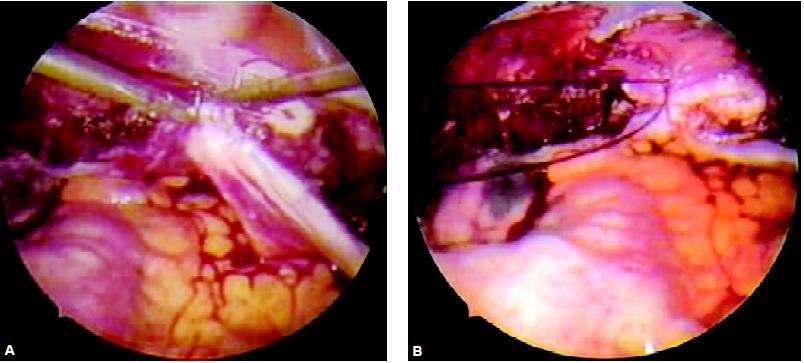

Dissection of bladder peritoneum

The ureterovesical junction is identified, grasped, and elevated with forceps while being cut with scissors. The bladder pillars are identified as desiccated and cut. The bladder can be completely freed from the uterus by pushing downward with the tip of a blunt probe along the vesicocervical plane until the anterior cul-de-sac is exposed completely. In patients with severe anterior cul-de-sac endometriosis, previous CS or adhesions, sharp dissection can be performed. Injecting 5 ml of indigo caramine in the patient’s bladder helps to detect bladder trauma. After dissecting the bladder from the uterus, the uterine vessels are identified desiccated and cut to free the lateral border of the uterus. If sutures, clips or linear staplers are used, it is important to fully skeletonize the vessel. As the uterine vessel is grasped and cut, the safety and position of the ureter should be checked. Ureter injury can be completely nullified if a ureteric catheter is introduced before the procedure. Cardinal ligament dissection must be carefully done as ureter and uterine artery falls just lateral to that. The linear stapler can be used only if the parametrium has been dissected with ample margins. Once the ureter is displaced laterally, the cardinal ligament tissue closest to the cervix is electrodesiccated and transacted. Alternatively, the linear stapler can be applied both on the uterine vessels and cardinal ligament.

Opening of anterior and posterior leaf broad ligament